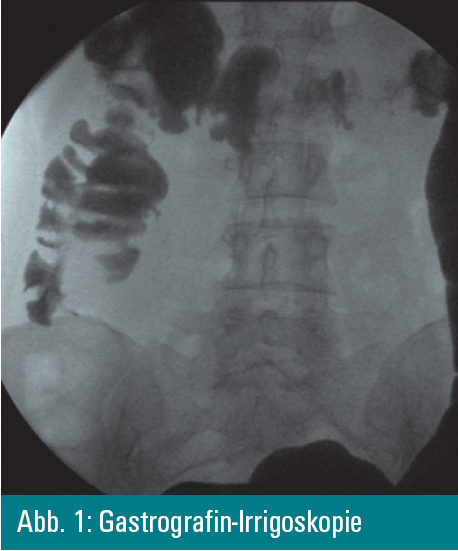

bestätigt die Invagination, die mittels einer Gastrografin-Irrigoskopie

gelöst wird. Die angeschlossene Colonoskopie führt zur Diagnose.